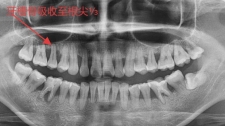

38岁的李先生最近有个难言之隐:每天早上刷牙,牙刷上总沾着血丝,吃个梨都能在果肉上留下血丝。他以为是最近“熬夜上火”,直到同事开玩笑说“你嘴里有股怪味...